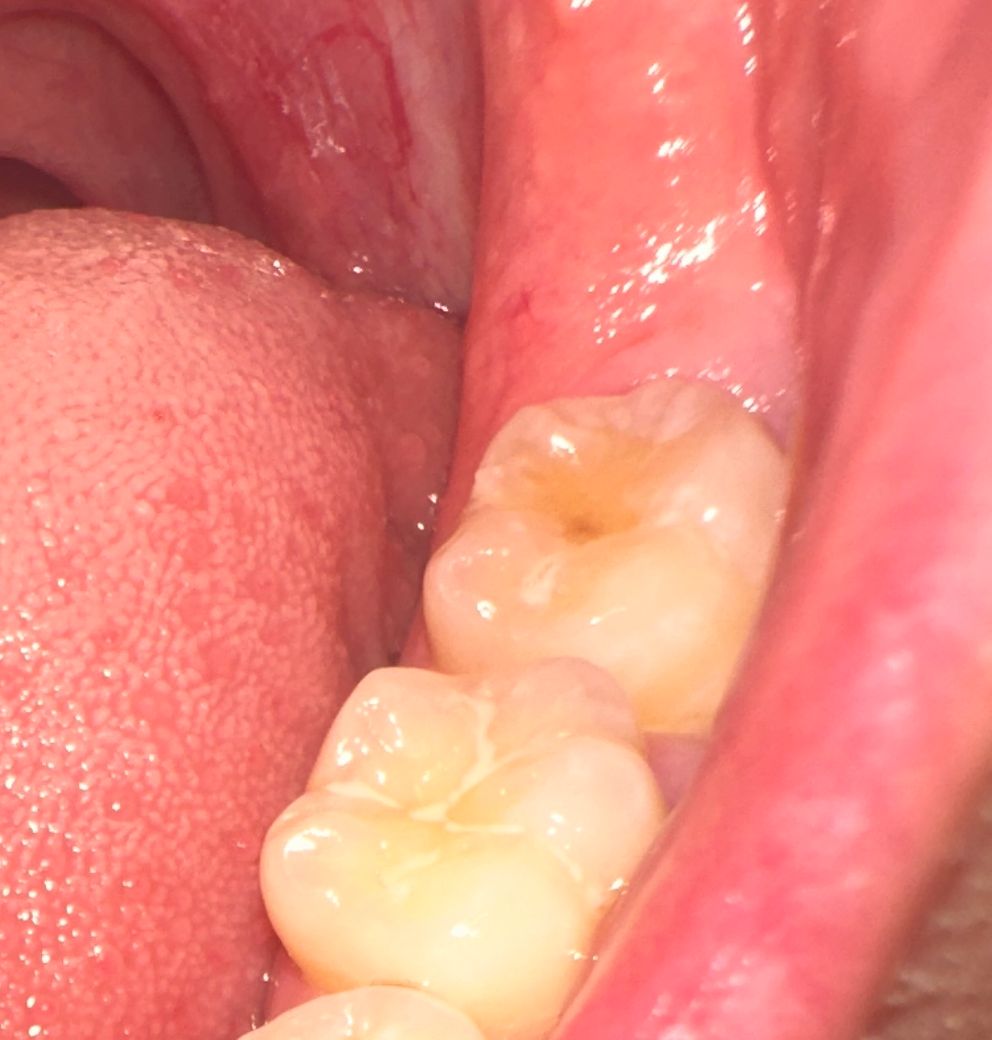

한달 전 가장 안쪽 어금니에 레진 치료를 받았었습니다.그 뒤 매일 식사 후 30분 뒤 양치하는 등 엄격하게 관리하고 있었는데 오늘 다시 확인해보니 치아 중앙에 저런 갈색 구멍인지 점인지 갈색으로 변색되어 있는 것이 있어 저게 다시 충치가 생긴 것인지 궁금합니다!

충치의 양상은 아닌 것 같고 변색 같습니다. 레진을 심혈을 기울여서 하는 치과의사중에서는 자연스러운 느낌을 부여하기 위해 레진 마무리 후 스테인(얼룩)을 의도적으로 넣기도 합니다.

레진부위에 착색이 된 것으로 보이며, 만약 통증이 동반되는 경우에는 충치 가능성이 있기에 보다 정확한 원인 확인을 위해 치과 진료를 받길 권합니다.

사진으로 보기에는 사실 충치가 다시 생겼다고 보기 애매하긴 합니다만 방사선사진과 임상검사를 해봐야 알 수 있겠습니다. 한달안에 잔존된 충치가 갑자기 저렇게 커지는 경우는 거의 없으므로 치료 받으셨던 곳에 다시한번 내원해보시길 바라겠습니다.

기존에 치료를 햇던 레진이 떨어져 나간거 같습니다. 치과에 가셔서 체크를 받아보시는게 좋을것같습니다.

사진으로 봤을 경우에는 크게 문제가 없는 것으로 보입니다. 레진하고 난 다음에 색이 변한 것처럼 보일 순 있습니다.